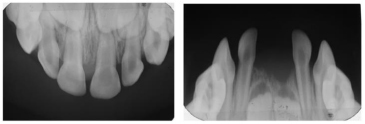

A 3-year-old female patient presented to a dental practice in Lesvos, Greece, in 2015, following the exfoliation of her lower primary central incisors shortly after their eruption. According to her parents, this was initially believed to be self-induced, prompting them to seek dental consultation. Clinical examination revealed intact roots on the exfoliated teeth, no gingival inflammation or bleeding, and no mobility of the other teeth. These findings were consistent with cementum deficiency rather than inflammatory periodontal disease. Anthropometric measurements were within the normal range for age and sex, and family history was negative for premature loss or metabolic disorders. Upper and lower occlusal radiographs were obtained to assess the status of her dentition (Fig. 1). Based on the clinical findings and history, hypophosphatasia (HPP) was suspected, and the child was referred to the hospital for diagnostic workup. Metabolic testing revealed markedly elevated plasma pyridoxal-5′-phosphate (PLP) levels, consistent with tissue-nonspecific alkaline phosphatase deficiency.

Upper and lower occlusal radiographs at age 3, following exfoliation of the mandibular primary central incisors, demonstrating a normal eruption pattern and absence of pathological changes.